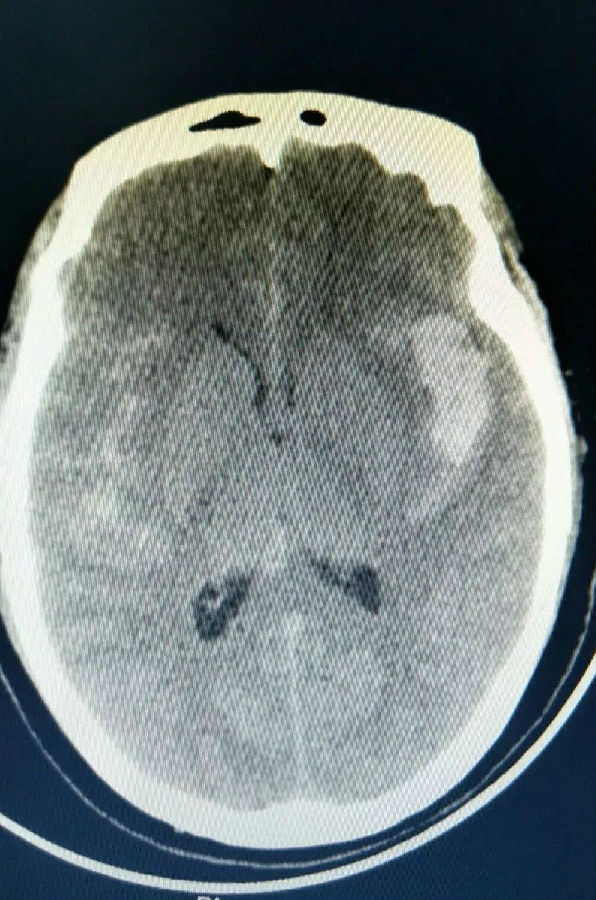

右外侧裂血肿

蛛网膜下腔出血

▲术前CTA显示右大脑中动脉动脉瘤

经64排CT血管造影进一步确诊,患者为颅内右外侧裂血肿,蛛网膜下出血。李要辉及时将造影显示的图像发给谭占国教授查看,远程接受治疗指导。